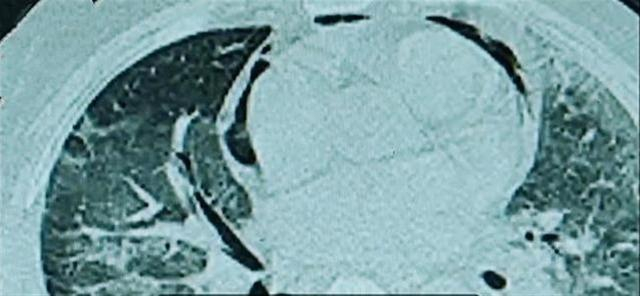

据第一帮帮团消息,福州一男子在家开启半年未清洗的空调,连吹两天后开始咳嗽不止。咳嗽两天后一度神志不清,出现呼吸衰竭被送进医院ICU。该男子被确诊感染了“嗜肺军团菌”,出现大面积“白肺”,肺部有多处坏死、空洞。